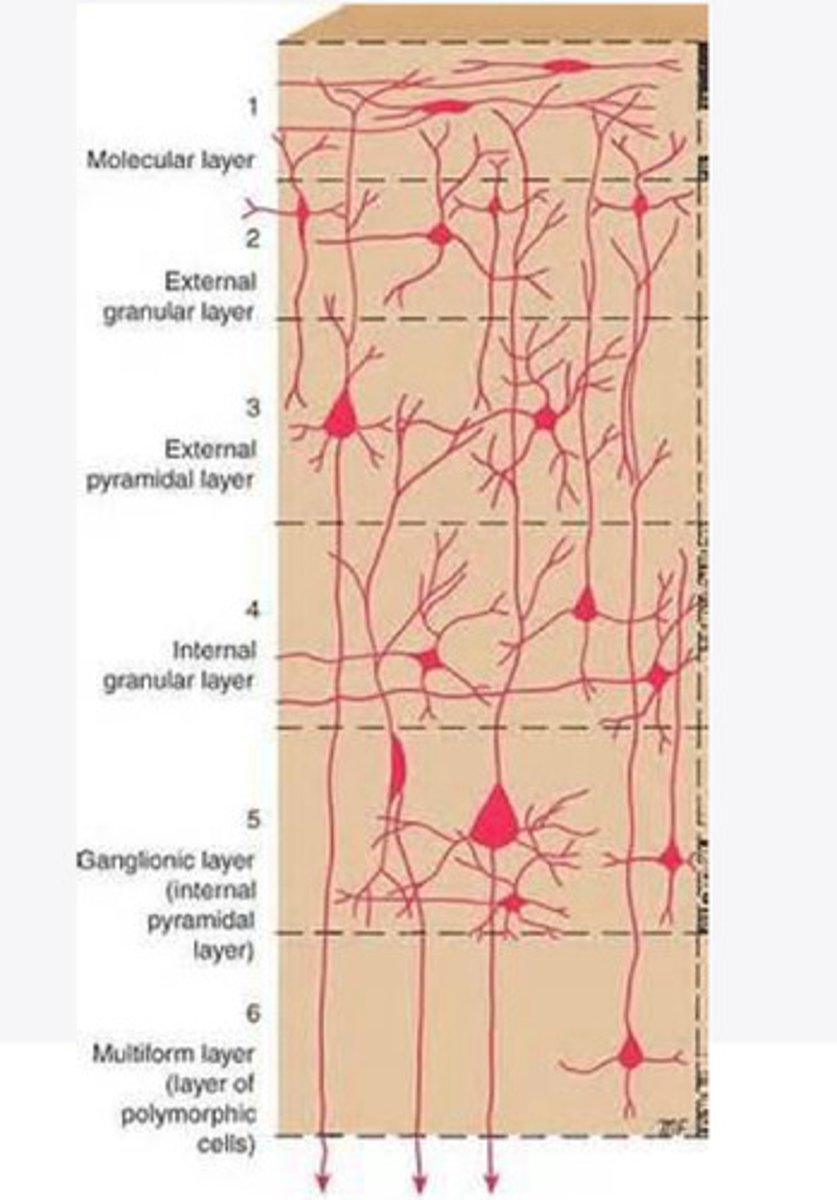

divided into 6 distinct layers, due to varying densities of cell body types within each layer

The cortex of the brain is divided into how many layers? Why is it divided into layers?

stellate, pyramidal

What are the 2 primary cell types in the cortex of the brain?

Layers of the cortex of the brain pic

stellate cells

These cells of the cortex RECEIVE impulses from other areas. There are numerous dendrites

in the regions of cortex associated with signal input

Where are stellate cells heavily concentrated in the cortex of the brain?

pyramidal cells

These cells of the cortex SEND impulses to other areas. Have 1 apical and 2 basal dendrites with a large axon

in regions of the cortex associated with sending output

Where are pyramidal cells heavily concentrated in the cortex of the brain?

2 and 4

What are the layers of the cortex that are associated with input?

3 and 5

What are the layers of the cortex that are associated with output?

molecular layer

What is the name of Layer 1 of the cortex of the brain?

very few cells

Does Layer 1 of the cortex have a lot or few cells?

receives dendrites from internal layers so it may actually function as a coordinating center where layers can communicate action

What does Layer 1 of the cortex do?

1

Every layer sends densities to Layer ____?

1

What layer serves as the "water cooler" of the brain?

external granular layer

What is the name for layer 2 of the cortex of the brain?

receives input from other cortical regions

What is the function of Layer 2 of the Cortex of the brain?

Stellate

What type of cells (stellate/pyramidal) would be most concentrated in Layer 2?

external pyramidal layer

What is the name for layer 3 of the cortex of the brain?

sends output to the other cortical layers

What is the function of Layer 3 of the cortex of the brain?

pyramidal

What type of cells (stellate/pyramidal) would be most concentrated in Layer 3 of the brain?

Layers 2 and 3

What layers are associated with association and commissural fibers?

Layer 3 - axons of cell bodies

Layer 2 - synapse into target areas in Layer 2

What part of the axons is in Layer 2/ in layer 3?

Layer 3 - external pyramidal layer

All axonal cel bodies for association and commissural fibers lie within what layer of the Cortex of the brain?

internal granular

** or called the striate cortex because it is so thick that you can see a line through this layer even in unstrained brain slides

What is the name for the 4th layer of the cortex of the brain?

receives input from the thalamus, geniculocortical layer, and other brainstem areas

What is the function for the 4th layer of the Cortex of the brain?

very thick within the vision, auditory, and somatosensory areas

Is Layer 4 thick or thin within SENSORY areas of the cortex?

Internal pyramidal

What is the name for Layer 5 of the cortex of the brain?

sends axons to the brainstem (corticobulbar) and spinal cord (corticospinal)

What is the function of Layer 5 of the cortex of the brain?

in motor areas of the cortex?

Where is layer 5 very thick in the brain?

the frontal lobe -- very motor heavy

What lobe of the brain will have a thick layer 5 of the cortex of the brain?

the multiform layer

What is the name of layer 6 of the cortex of the brain?

-sends axons back to the thalamus through corticogeniculate fibers

-modulates what information the thalamus sends to the cortex to control the strength of the signal received and modulate what you pay attention to

What is the function of layer 6 of the cortex of the brain?

no

Is layer 6 a motor layer?

without knowledge?

What are a priori decisions?

Yes, Layer 6 allows the cortex to make these decisions with corticogeniculate fibers

Can Layer 6 of the cortex of the brain make a priori decisions?

Symptoms experienced by TBI

Damage to Layer 6 of the cortex of the brain can play a role in what symptoms?